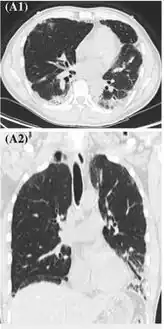

There are non-specific laboratory abnormalities that have been reported in association with the disease, including elevations in white blood cell count (with neutrophilic predominance and absence of eosinophilia), transaminases, procalcitonin, and inflammatory markers.[4][59] Infectious disease testing, including blood and sputum cultures and tests for influenza, Mycoplasma, and Legionella were all found to be negative in the majority of reported cases.[59] Imaging abnormalities are typically bilateral and are usually described as "pulmonary infiltrates or opacities" on chest X-ray and "ground-glass opacities" on chest CT.[4]

-

High-resolution computed tomography reveals patchy consolidation, ground-glass opacification in bilateral lower lungs -